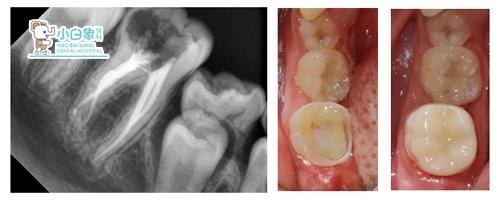

隔湿干燥,根管内置牙胶尖+根管糊剂充填根管,

Z350垫底,制备牙体,扫像,设计,研磨,试戴,

隔湿干燥,粘结嵌体。